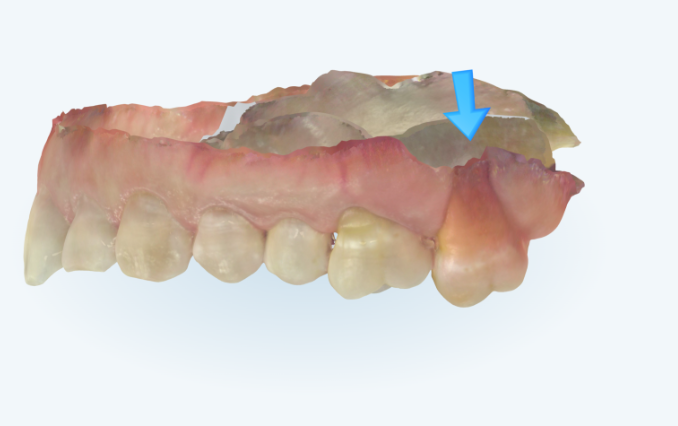

내려와 있던 제 1대구치가 원래위치로 많이 올라갔습니다.

이제 임플란트 심을 공간이 확보되었습니다.

입천장에 교정용 나사인 미니스크류를 1개 심고 정출된 제1구치 함입을 도모합니다.

빈공간으로 내려와있던 큰어금니를 함입시켜 비로소 임플란트 심을 공간이 확보되었습니다.

바로 뒤에 발치시기를 미루고 치료에 이용된 제 2대구치는 임플란트 수술과 함께 발치할 예정입니다.